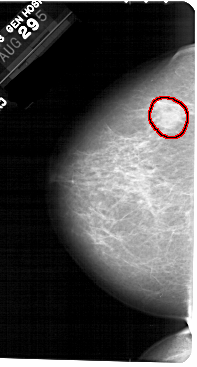

A_1347_1.LEFT_CC

LEFT_CC LINES 5491 PIXELS_PER_LINE 2941 BITS_PER_PIXEL 12 RESOLUTION 43.5 OVERLAY

FILE: A_1347_1.LEFT_CC.OVERLAY

TOTAL_ABNORMALITIES 1

ABNORMALITY 1

LESION_TYPE MASS SHAPE IRREGULAR MARGINS ILL_DEFINED

ASSESSMENT 4

SUBTLETY 2

PATHOLOGY BENIGN

TOTAL_OUTLINES 1

BOUNDARY